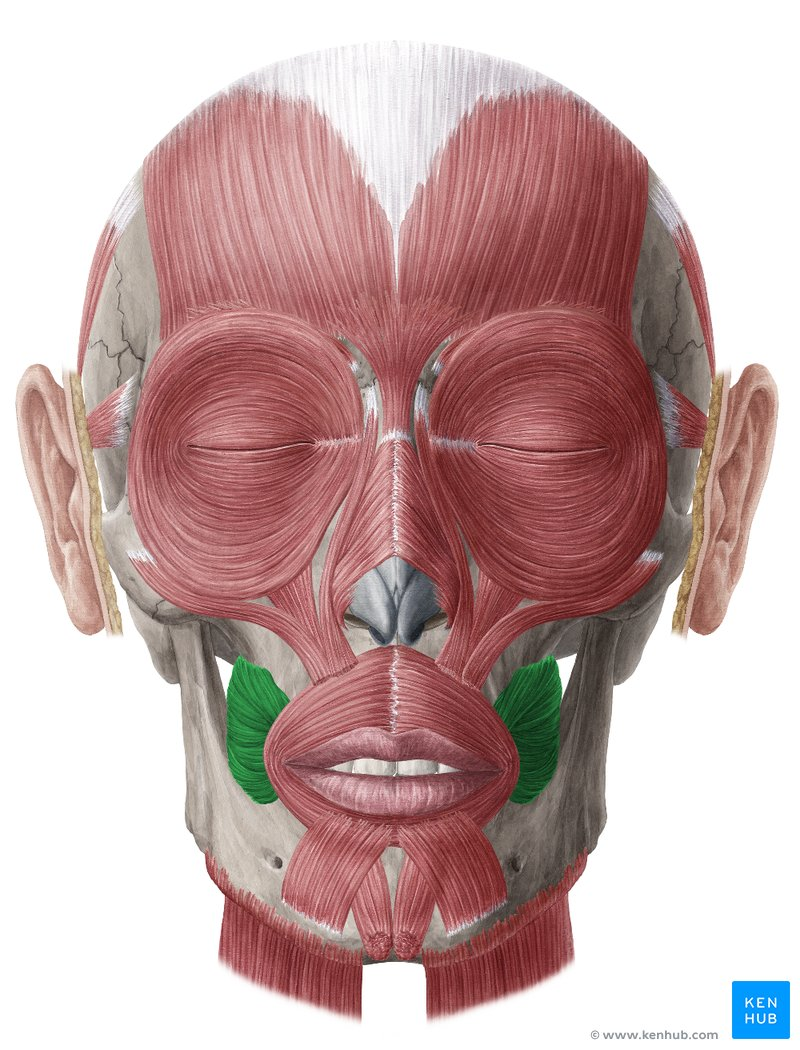

m buccinator

Rör kinderna